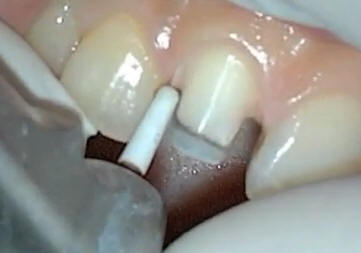

Tallado de las caras

mesial y distal con puntas de diamante troncocónicas de

extremo redondeado |